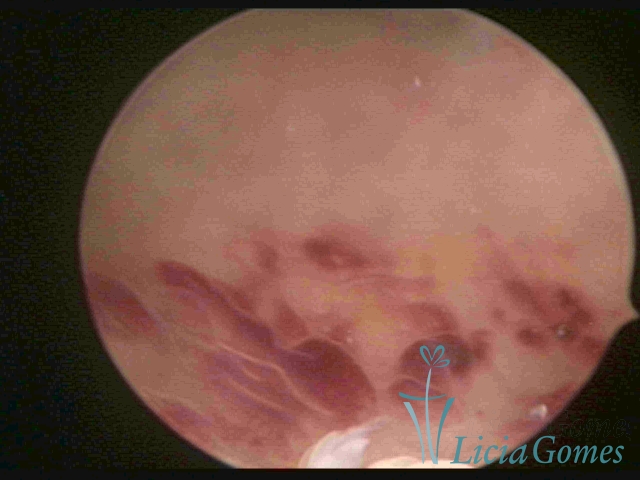

ENDOMETRITE AGUDA

Na vídeo-histeroscopia observamos o endométrio sangrante, sua superfície endometrial é espiculada, com aspecto “cremoso” e coloração esbranquiçada com brilho acentuado pela fibrina acumulada. Áreas azuladas ou acidentadas que podem corresponder à necrose cística. Pode haver muco aderente ou piometra.